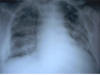

Fibrosis pulmonar. ICC.